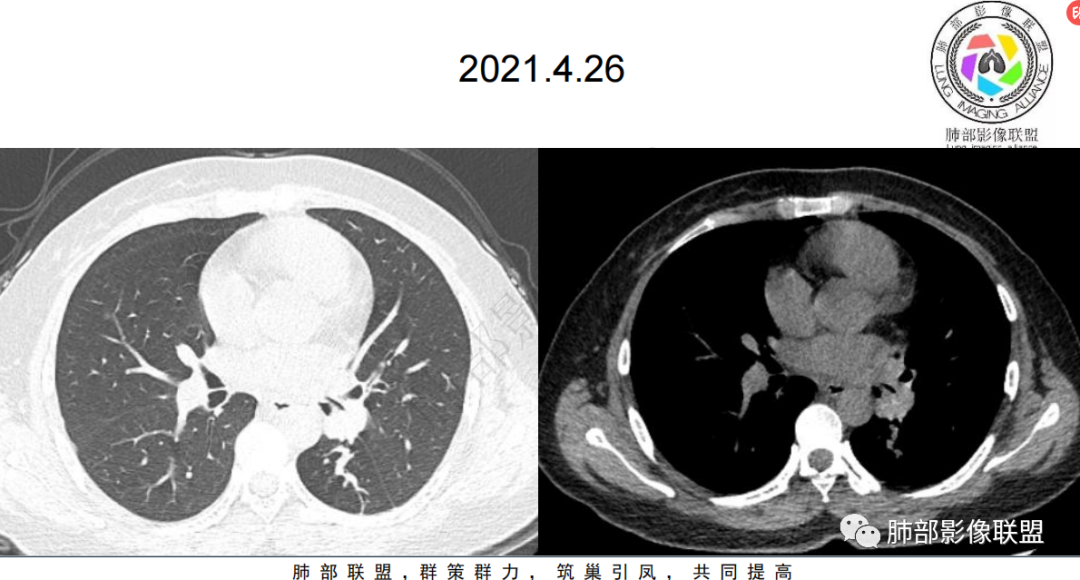

年轻女性 咯血 病史3年。

左肺门及下叶不规则实性结节,明显强化。3年前就有病灶,可对比一下。

左肺门肿块,包绕支气管生长,部分突向支气管内,形态欠规则,边缘清楚,平扫密度均匀,增强扫描不均匀强化,远端胸膜下可见一实性结节,内部可见空泡,增强扫描不均匀强化,考虑恶性,小细胞肺癌?腺癌,类癌?

女,31岁,间断咳嗽咳血3年余,左肺下叶胸膜下见实性结节影,边界清晰,期内见小空泡影,病灶呈宽基底与胸膜相连,病灶周围见少许斑片影,左侧肺门见不规则形肿块影,边界清晰,考虑结核可能,鉴别腺癌。

青年女性,间断咳嗽、咯血3年,再发半天,炎性指标、血沉全正常。左下肺近肺门结节,跨叶裂,膨隆分叶,支气管门口截断,平扫密度高,有钙化,增强后强化明显,未见明显坏死及淋巴结肿大,稍远端支气管内低密度影,增强化强化不明显,左下叶后基底段胸膜下结节,内有小空洞,强化明显。思路:一、感染性病变:1、整体一元考虑结核,病史反复三年咳嗽,咯血三年支持,左肺门病灶跨叶伴远端支气管内粘液栓及左下肺胸膜下伴小空洞结节均支持,疑点:前两次发作抗感染治疗均有效好转,本次炎性指标及血沉等均正常不好解释。支气管门口截断不好解释,反复发作三年,无肿大淋巴结不好解释。2、慢性非特异性炎伴机化。病史三年反复,发作时抗感染治疗有效,要考虑。二、肿瘤:1、腺癌,肺门区及胸膜下多中心腺癌,膨隆、分叶,支气管门口截断,强化明显均支持,胸膜下结节强化明显支持,反复发作的症状考虑合并阻塞性炎症。2、类癌,平扫密度较高,有钙化,强化明显支持,3、涎腺类肿瘤,性别年龄要考虑,但增强明显较均匀强化不太支持。4、淋巴瘤,影像表现要考虑,但这个年龄段的淋巴瘤一般为HD,这个不符合。所以可能小。5、极端的二元肿瘤,肺门区类癌,胸膜下腺癌。三、非肿瘤非感染性病变,血管炎,反复发作三年的症状,有过敏性鼻炎,要考虑,需要查血管炎三项和副鼻窦情况排除。临床很简单:下一步EBUS穿刺肺门区及经皮穿刺胸膜下结节。至于读片嘛,还是先考虑恶性(腺癌>类癌>二元癌>淋巴瘤),鉴别诊断:结核>非特异性炎伴机化>血管炎

平扫密度偏高,60HU,增强后有强化,88HU